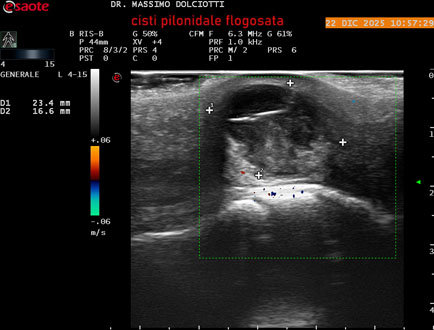

Data inserimento: 24/12/2025

Ecografia del: 22/12/2025

Strumento: Esaote MyLab Eight

Sonda: Lineare Multifrequenza 4-15 MHz

Età Paziente: M 29 anni

Motivazione dell'esame: da 3.giorni dolore, tumefazione ed arrossamento in regione coccigea

Commento all'esame: le immagini ed il video documentano formazione anecogena in sede coccige, delle dimensioni di 24,6 x 18,8 mm, da ricondurre a cisti pilonidale flogosata.

Conclusioni: cisti pilonidale flogosata (inflamed pilonidal cyst).